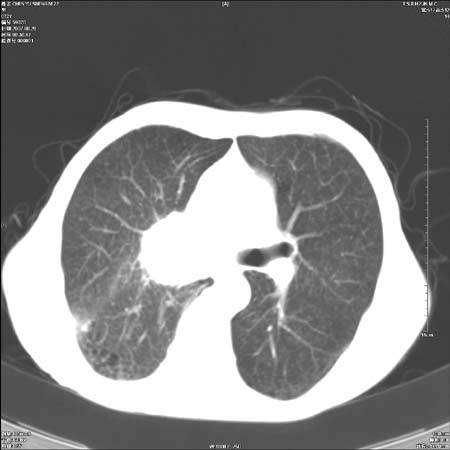

男性,72岁,既往肺结核,今复查。无前片对比。

纵隔窗

右侧中央型肺癌伴中叶不张可能性大,建议增强扫描.右上肺陈旧性肺结核.慢性支气管炎伴肺气肿.右侧少量胸腔积液.

右侧中央型肺癌伴中叶不张可能性大,建议纤支镜检查.右上肺陈旧性肺结核.肺气肿。

典型右肺中心型肺癌

右侧中央型肺癌伴肺不张可能性大,建议增强扫描.右上肺陈旧性肺结核.慢性支气管炎伴肺气肿.右侧少量胸腔积液.

右肺中心型肺癌

右侧中央型肺癌.上肺陈旧性肺结核.

1右侧中央型肺癌伴中叶不张2右侧少量胸腔积液3右上肺陈旧性肺结核

1.右肺中心性肺癌并右肺中叶综合征2。右侧胸腔少量积液3。右肺上叶结核球已钙化,4。慢支伴肺气肿

右侧中央型肺癌伴中叶不张可能性大,建议纤支镜检查.右上肺陈旧性肺结核.肺气肿。

右侧中央型肺癌伴中叶不张可能性大,建议增强扫描.右上肺陈旧性肺结核.慢性支气管炎伴肺气肿.右侧少量胸腔积液.

右侧中央型肺癌伴中叶不张

右肺中央型肺癌伴右肺中叶不张。

右上肺陈旧性肺结核。

支持右肺中心型肺癌并中叶不张,右上肺陈旧性肺结核钙化,右侧少量胸腔积液。

支持右侧中央型肺癌伴中叶不张可能性大,建议增强扫描.右上肺陈旧性肺结核.慢性支气管炎伴肺气肿.右侧少量胸腔积液.

支持 1右侧中心型肺癌伴中叶不张2右侧少量胸腔积液3右上肺陈旧性肺结核4双肺局限性肺气肿

1,右侧中央型肺癌.

2,右上肺陈旧性肺结核.

1.右侧中央型肺癌伴中叶不张,建议纤支镜检查.

2.右上肺陈旧性肺结核.

3.肺气肿。

4.右侧少量胸腔积液.

右侧中央型肺癌伴中叶不张并纵隔淋巴结增大,建议增强扫描.右上肺陈旧性肺结核.慢性支气管炎伴肺气肿.右侧少量胸腔积液。

右肺中心型肺癌并肺不张,陈旧性肺tb.慢支,肺气肿.

陈旧性肺结核.慢性支气管炎伴肺气肿,中央型肺癌伴中叶不张。

右侧中央型肺癌伴中叶不张可能性大;右上肺陈旧性肺结核.慢性支气管炎伴肺气肿

陈旧性结核是存在,但真正致命的却是右侧中心型肺癌。